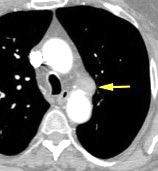

30 años

Borramiento de la banda PARA-aórtica por AdenoCa. de LII, no visible en 2005

Colapso de LII. TC: secreciones bronquiales.

Endoscopia tapón mucopurulento extraído

Borramiento parcial por Ca. epidermoide.